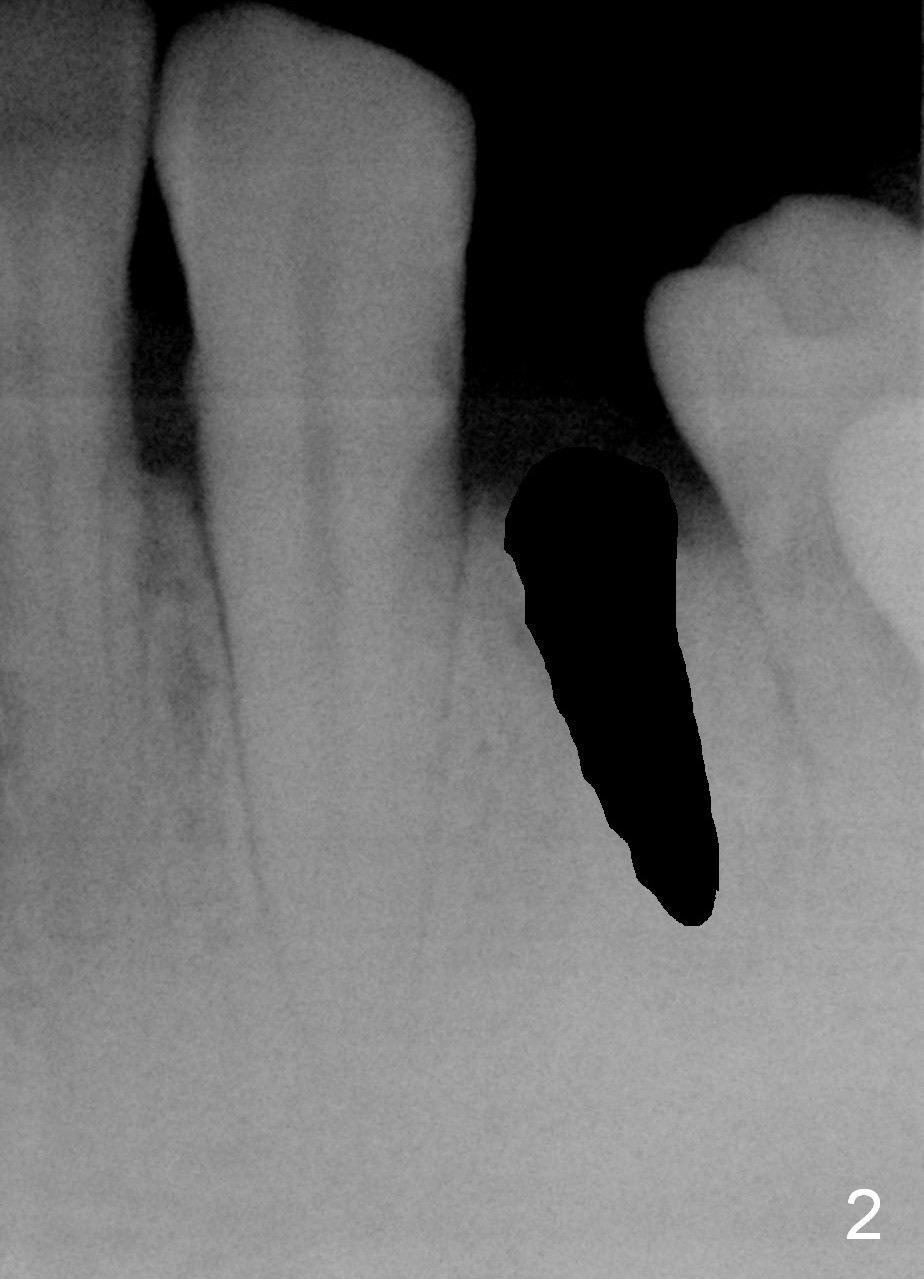

A 48-year-old man requests restoring the fractured tooth #21 (Fig.1). The socket seems to be oblique (Fig.2, no Antibiotic). Also considering the thin buccal plate, the initial osteotomy should be established in the mesiolingual slope (Fig.3). Change the trajectory once the entry is made (Fig.4) and take PA for confirmation. A 4x13 mm implant is to be placed (Fig.5). Why should the implant placed lingually? In fact the implant is placed too lingually. What is the reason?